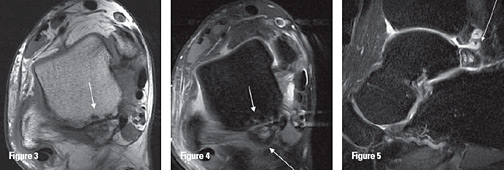

Figure 1: Os trigonum demonstrates lucent region (syndchondrosis) adjacent to the posterior talus; the Stieda process is a prominent posterior talar process remaining attached to the talus (note the bone cyst in the calcaneus).

When the os trigonum is the cause, it is described as os trigonum syndrome. Os trigonum is caused by the failure of fusion of the secondary ossification center which forms the posterolateral aspect of the talus. This secondary ossification center develops between the ages of 8 and 13 years. Normally this ossification center fuses with the rest of the talus within one year. If it fails to fuse, an os trigonum is formed that articulates with the talus via a synchondrosis.1,3-4 (This is a good reason to recommend that young female ballet dancers not be put en pointe before 14 or 15 years old.)

Radiographs can be helpful revealing an os trigonum or Stieda process. Lateral radiographs obtained with the foot in plantarflexion may demonstrate the os trigonum or lateral talar tubercle impinged between the posterior-tibial malleolus and the calcaneal tuberosity.1 MR imaging is the modality of choice for further evaluation of the bony and soft-tissue structures.